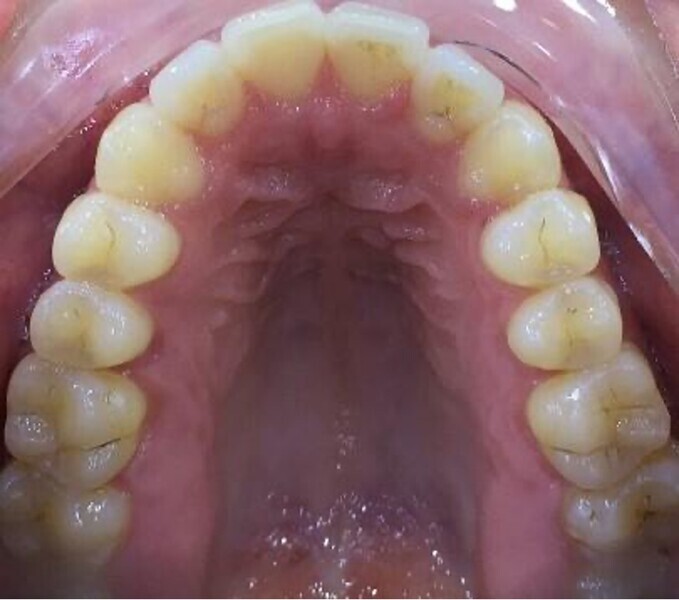

The patient presented with the goal of enhancing her smile. She had a narrow smile, bilateral posterior crossbite and an anterior crossbite with tooth #12. From the extra-oral perspective, the patient was also wider on the right vertical fifth (Figs. 25–28). The treatment objective was to correct the anterior crossbite and posterior crossbite and to simultaneously correct the asymmetrical buccal corridors by further broadening the arch on the right more than the left. Once the alignment had been completed, the case was finished with in-chair tooth whitening and composite augmentation of teeth #12 and 22 (Figs. 29–31).

Fig. 31: Occlusal view of the maxillary arch after aligner treatment.